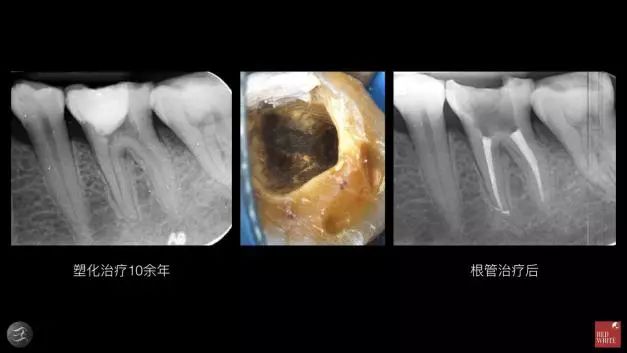

▲如上图两个转诊过来的病例都已经治疗10余年,患者没有任何症状,第二个根管治疗后反而出现了自发性地隐痛。